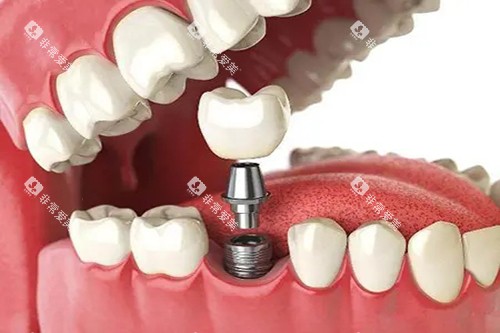

牙周病是成年人牙齿脱落主因,种植体周围炎则威胁种植牙寿命,二者根源均为细菌生物膜。

传统治疗难以穿透生物膜,易损伤正常组织,且复发率高。

冀城口腔采用的光动力技术,是国内外比较靠前的 “定向杀菌” 方案:将光敏剂涂抹病变部位,其优先被有害细菌吸收,再用特定波长光照射促活,产生活性氧精密杀菌,不损伤正常组织。

该技术优势显著:其一,不痛舒适,无需手术,患者轻松完成治疗;其二,较高的效率杀菌,破坏生物膜,控制炎症、促进愈合,延长种植牙寿命 5-10 年;其三,靠谱无耐药性,物理杀菌无需抗生素,对老人、儿童友好。